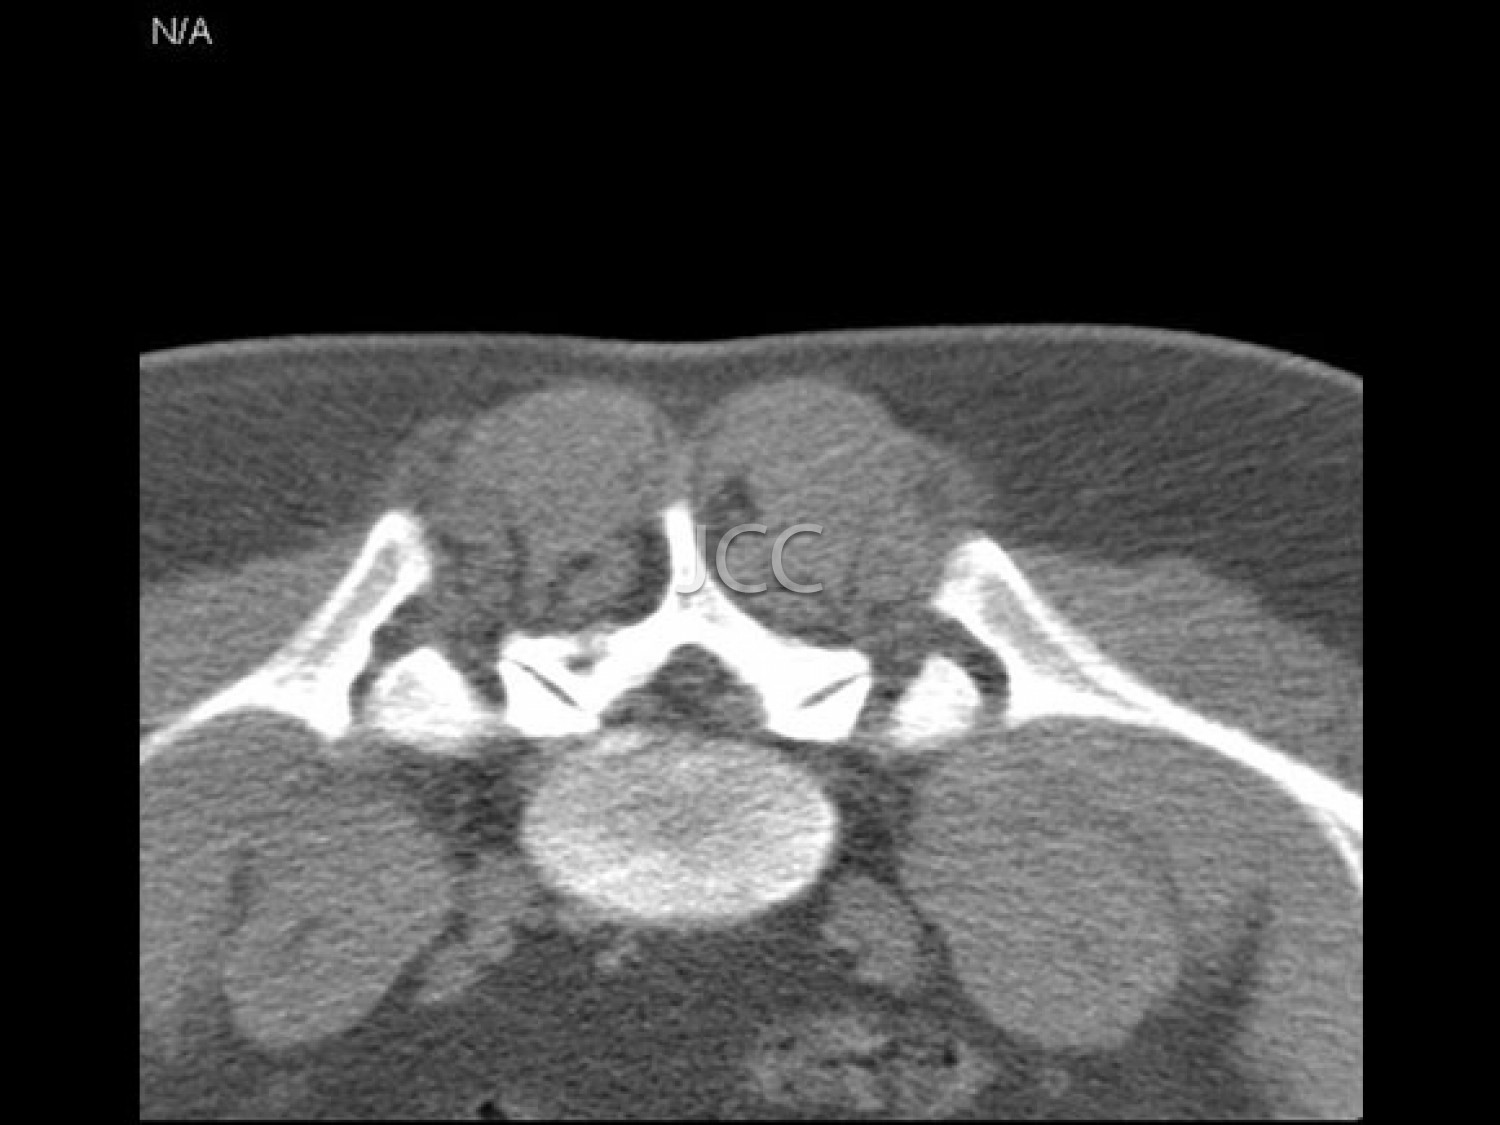

- Interventional Radiology